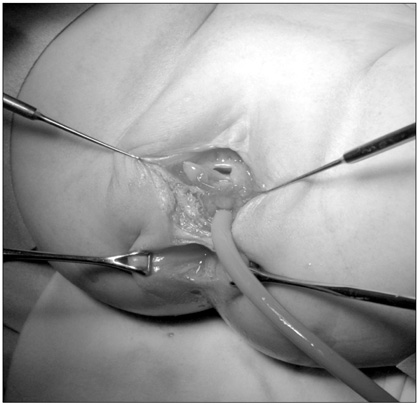

A 2-month-old female infant presented to our hospital with a 1-month history of stool passing through the vagina. She was born at 36 weeks' gestation weighing 1.875 kg and was the second infant of a twin. She had a ventricular septal defect that closed spontaneously at 1 month of age. Initially, she was diagnosed with a rectovaginal fistula. Despite conservative therapy, including a sitz bath, for 5 months, there was no improvement in her symptoms, and most of the stool still appeared to pass through the vagina. A colon study indicated a rectovaginal fistula directly connected to the distal rectum (

Fig. 1). Under general anesthesia, a small opening located posterior to and near the vagina at vestibule was found. The structure that had been misdiagnosed as a fistula based on the colon study was not present. The patient had a normally sited anus, an anterior ectopic anus, and a double vagina (

Fig. 1A preoperative colon study appeared to show that the contrast had passed to the vagina through a rectovaginal fistula (arrows).